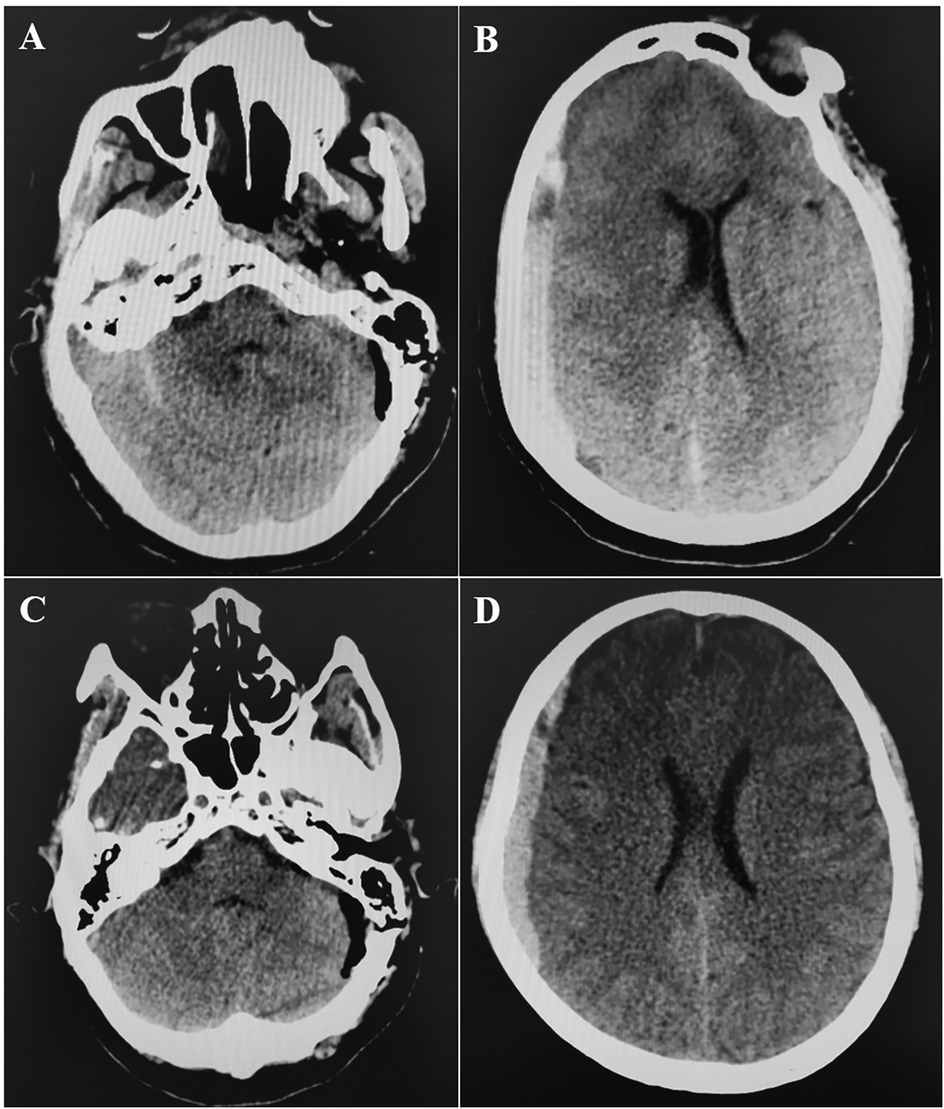

A retrospective review of 480 patients who underwent MVD for hemifacial spasm, trigeminal neuralgia, or glossopharyngeal neuralgia at our hospital from February 2008 to March 2019 identified one instance of acute brain swelling due to supratentorial subdural hematoma. This case involved a 60-year-old woman with a five-year history of trigeminal neuralgia and no hypertension, coagulopathy, or systemic diseases. During surgery, she was positioned laterally, and the arachnoid membrane was routinely opened. Cerebrospinal fluid (CSF) drained slowly, causing slight cerebellar collapse. Ten minutes after dura entry, the cerebellopontine cistern was opened, leading to a sudden CSF gush and almost immediate acute brain swelling, filling the surgical field within 10 s (Supplementary Video S1). Throughout, the patient's head position remained unchanged, blood pressure and heart rate were stable, anesthesia was maintained, and the procedure followed standard protocols without any unusual circumstances. The cause of the brain swelling was unclear, given normal manipulation, unobstructed airway, and absence of surgical bleeding. We had to manage the brain swelling while considering the possibility of remote hemorrhage. Mannitol (250 ml ivgtt) and dexamethasone (10 mg i.v.) were administered to lower intracranial pressure (ICP), while cerebrospinal fluid was gradually drained from the compact subdural space. The surgical field was restored within 40 min, and ICP gradually decreased. Despite the surgical field being narrower than initially, and elevated ICP detected under the suction device, we proceeded with supracerebellar artery decompression of the trigeminal nerve in a confined space (Supplementary Video S2). Bilateral pupil monitoring during surgery showed normal results. A postoperative CT scan immediately revealed contralateral acute supratentorial subdural hematoma (SDH) with a midline shift of approximately 4 mm (Figure 1). The patient awoke from anesthesia with a Glasgow score of 15, and no obvious signs of neurological dysfunction were observed. Moreover, within 8 h after the operation, three head CT scans were completed, confirming that the volume of the subdural hematoma remained stable and did not increase further. At the same time, the patient's clinical symptoms were stable, with no obvious symptoms of increased intracranial pressure such as headache or projectile vomiting. Therefore, we did not place an ICP probe for continuous monitoring of intracranial pressure, but continued to observe the clinical symptoms and signs. Fortunately, when the CT was rechecked 21 h after the operation, it was found that most of the subdural hematoma had dissipated (Figures 2A,B). The patient was discharged eight days later without neurological impairments.

Figure 2

CT scan showing two different brain images. Image A displays a horizontal cross-section of the brain, highlighting asymmetrical features. Image B presents a more symmetrical brain structure with clear differentiation between the gray and white matter.

Figure 2. (A,B) CT at 21 h post-operation showed that the right subdural hematoma was significantly dissipated.